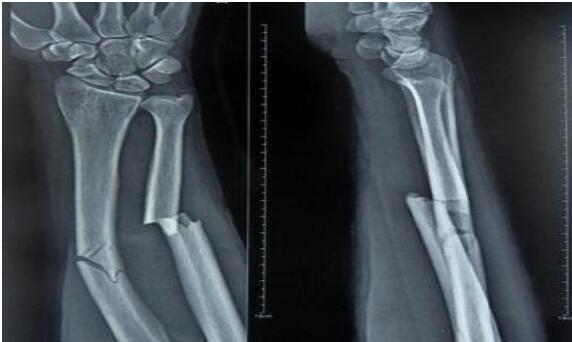

山丹接骨法是一種民間治療手段。山丹縣東樂(lè)鄉(xiāng)村民姜多明師從其父,掌握了接骨這門民間絕技。姜多明家族接骨已有上百年歷史,其父親是東樂(lè)一帶有名的中醫(yī)。改革開(kāi)放前,由于農(nóng)村醫(yī)療條件有限,這一技術(shù)在農(nóng)村發(fā)揮了很大作用,給人民群眾減輕了不少身體上的痛苦。這項(xiàng)接骨技術(shù)同時(shí)也適用于給牲畜接骨。骨折愈合過(guò)程是一個(gè)高度復(fù)雜和有序的精細(xì)過(guò)程,姜多明所用的中醫(yī)傳統(tǒng)接骨法對(duì)骨折愈合起到了其他藥品不可替代的作用,效果很好。這種傳統(tǒng)的接骨方法極為簡(jiǎn)潔,不用石膏,只用中草藥加雞蛋清,中藥主要起治療作用,蛋清起固定作用。治療周期較短,小孩子7—8天,傷勢(shì)較重的最多1月;成人根據(jù)傷勢(shì)而定,最多40—50天;牲畜所用天數(shù)根據(jù)情況而定。 2010年7月6日,山丹接骨法(民間傳統(tǒng)接骨法)被張掖市人民政府列入第二批張掖市非物質(zhì)文化遺產(chǎn)代表性項(xiàng)目名錄。保護(hù)單位:張掖市山丹縣文化館。